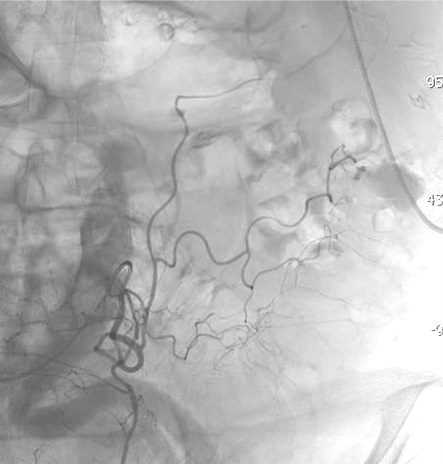

病例一

病例二 Onyx